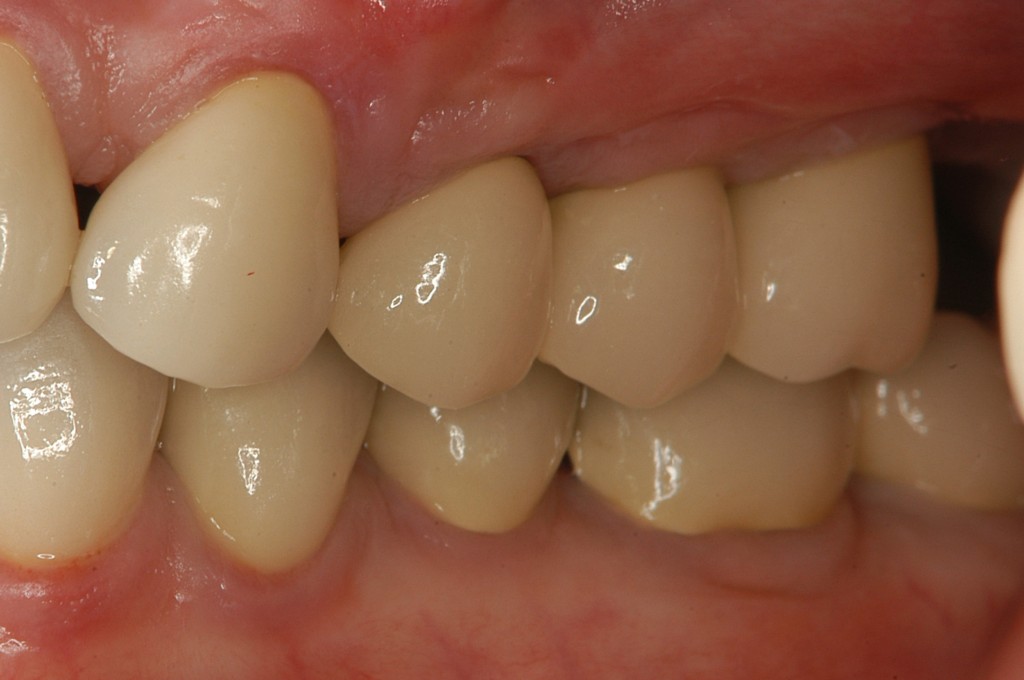

インプラントを埋入し,セラミックスクラウンを被せました。

奥歯でも食べ物を噛めるようになり,大変満足していただきました。